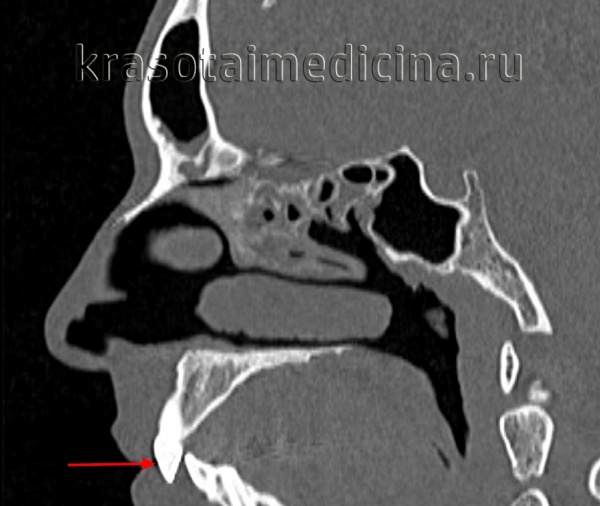

![КТ черепа (3D-рендеринг). Прогнатический прикус, зубы верхней челюсти (красная стрелка) выстоят кпереди, отсутствует контакт резцовых краев при смыкании.]()

КТ черепа (3D-рендеринг). Прогнатический прикус, зубы верхней челюсти (красная стрелка) выстоят кпереди, отсутствует контакт резцовых краев при смыкании.

![КТ черепа. Прогнатический прикус, зубы верхней челюсти (красная стрелка) выстоят кпереди (этот же пациент).]()

КТ черепа. Прогнатический прикус, зубы верхней челюсти (красная стрелка) выстоят кпереди (этот же пациент).